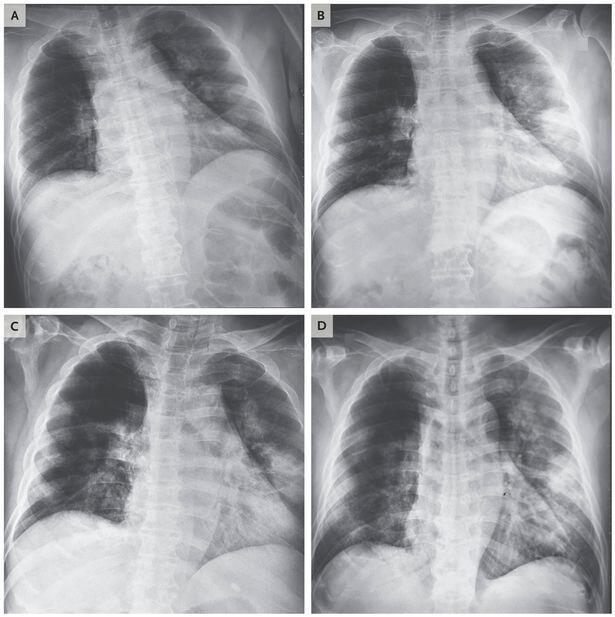

Koronavirus xəstələrinin ağ ciyər müayinəsini əks etdirən rentgen görüntüləri yayılıb.

Oxu24.com metbuat.az-a istinadla xəbər verir ki, koronavirusdan ölən şəxsin rentgen və komputer tamoqrafiya şəkillərində ağ ciyərlərin mərhələ-mərhələ necə məhv olduğu görünür.

Həmin görüntüləri təqdim edirik.